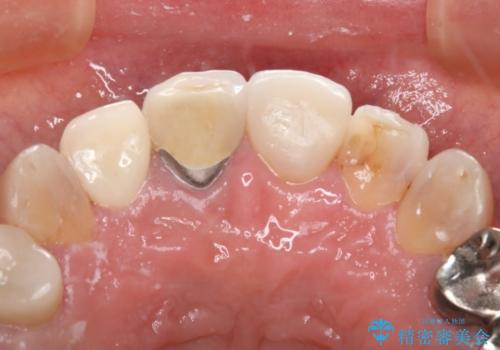

- 右上2番の審美性改善を主訴に来院された患者様です。

切削量と前歯ということからオールセラミッククラウンでの治療を選択しました。